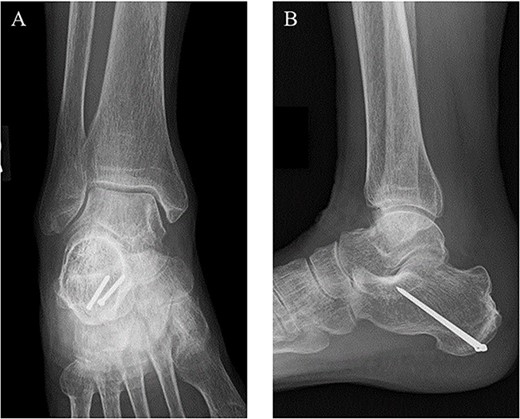

Postoperatively, a non-weightbearing short leg cast was applied for 2 weeks, and when the cast was removed, active and passive ranges of motion exercises of the ankle were started. Partial-weightbearing was allowed at 2 weeks postoperatively, and full-weightbearing at 6 weeks postoperatively. At 3 months after the surgery, non-contrast CT showed complete bone union (Fig. 4). At 2 years after the surgery, she had no symptoms and dysfunctions (Fig. 5).

At 3 months after the surgery, non-contrast CT showed complete bone union in a sagittal view.

At 2 years after the surgery, plain radiographs of the right ankle showed complete bone union without the deformity of the fracture site and the backing out of the implants in (A) anteroposterior and (B) lateral views.